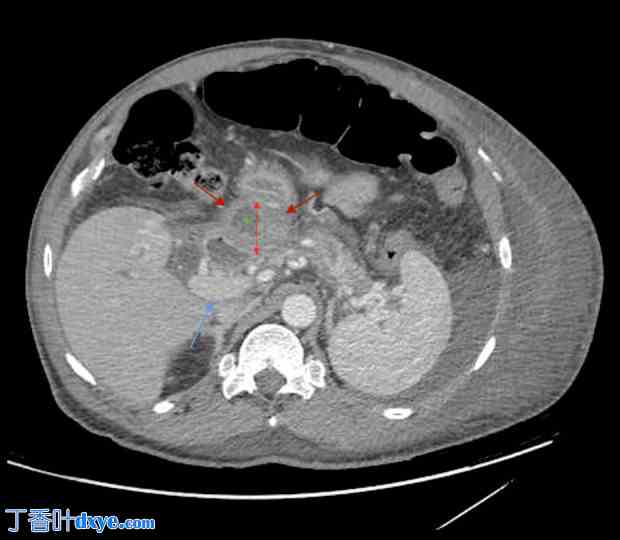

图 2.

2.jpg

腹部 CT 扫描显示一个 5.7×4.3 cm 的胰腺肿块(红色箭头)。此图为胰头肿块的第二个视图。